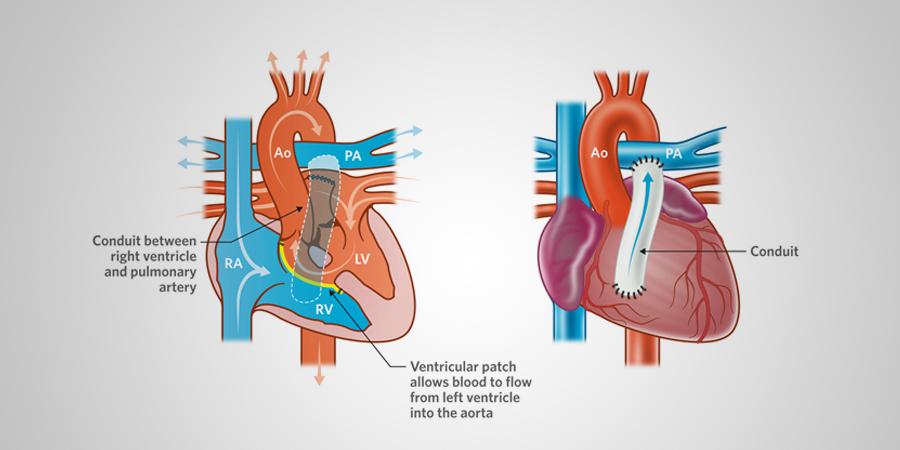

Overview

Package includes:

Days in hospital : 12 to 13 Days (For patient and one attendant)

Days in hotel : 16 Days (For patient and one attendant)

Room type in hospital : Shared

Room type in hotel : Private

Hotel category: Standard

Value added benefits of the Rastelli Procedure:

Ø Doctor consultation charges

Ø Lab tests and diagnostic charges

Ø Room charges inside hospital during the procedure

Ø Surgeon Fee

Ø Nursing charges

Ø Hospital surgery suite charges

Ø Anesthesia charges

Ø Routine medicines and routine consumables (bandages, dressings etc.)

Ø Food and Beverages inside hospital stay for patient and one attendant.

Extra benefits: